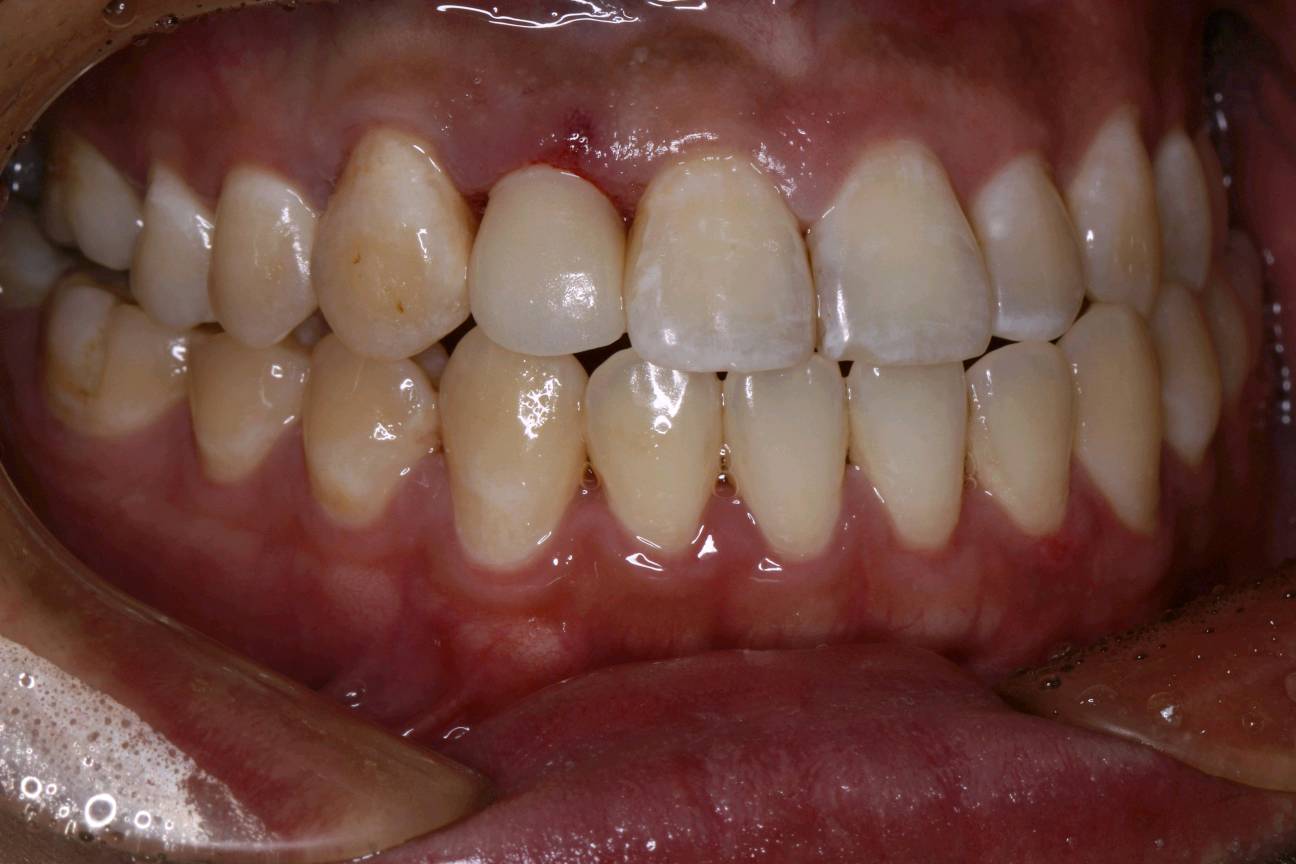

患者男三十岁,12近中邻面龋坏,经常性食物嵌塞,探+-,扣-,冷水入洞一过性敏感。牙面色泽偏黄,牙颈部呈白垩色。余无特殊。治疗计划:去腐+复合树脂充填+贴面修复。如果偶感食物嵌塞,还是要到口腔诊所及时就医检查。很有可能是发生龋坏,需要及时修复,如果出现疼痛的现象,就不能靠单纯的补牙修复那么简单了。所以每半年定期检查牙齿,才能避免出现严重的口腔疾病。通过西诺德口扫系统,3D打印口腔模型。当天上午备牙 下午即可佩戴。色泽形态自然,边缘密合,患者满意!

术前